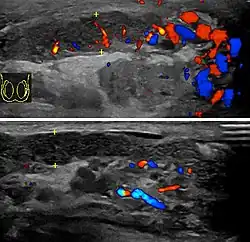

Doppler ultrasound of epididymitis, seen as a substantial increase in blood flow in the left epididymis (top image), while it is normal in the right (bottom image). The thickness of the epididymis (between yellow crosses) is only slightly increased.

Epididymitis usually has a gradual onset. Typical findings are redness, warmth, and swelling of the scrotum, with tenderness behind the testicle, away from the middle (this is the normal position of the epididymis relative to the testicle). The cremasteric reflex (elevation of the testicle in response to stroking the upper inner thigh) remains normal.[1] This is a useful sign to distinguish it from testicular torsion. If there is pain relieved by elevation of the testicle, this is called Prehn's sign, which is, however, non-specific and is not useful for diagnosis.[13] Before the advent of sophisticated medical imaging techniques, surgical exploration was the standard of care. Today, Doppler ultrasound is a common test: it can demonstrate areas of blood flow and can distinguish clearly between epididymitis and torsion. However, as torsion and other sources of testicular pain can often be determined by palpation alone, some studies have suggested that the only real benefit of an ultrasound is to assure the person that they do not have testicular cancer.[14]: p.237  Nuclear testicular blood flow testing is rarely used.